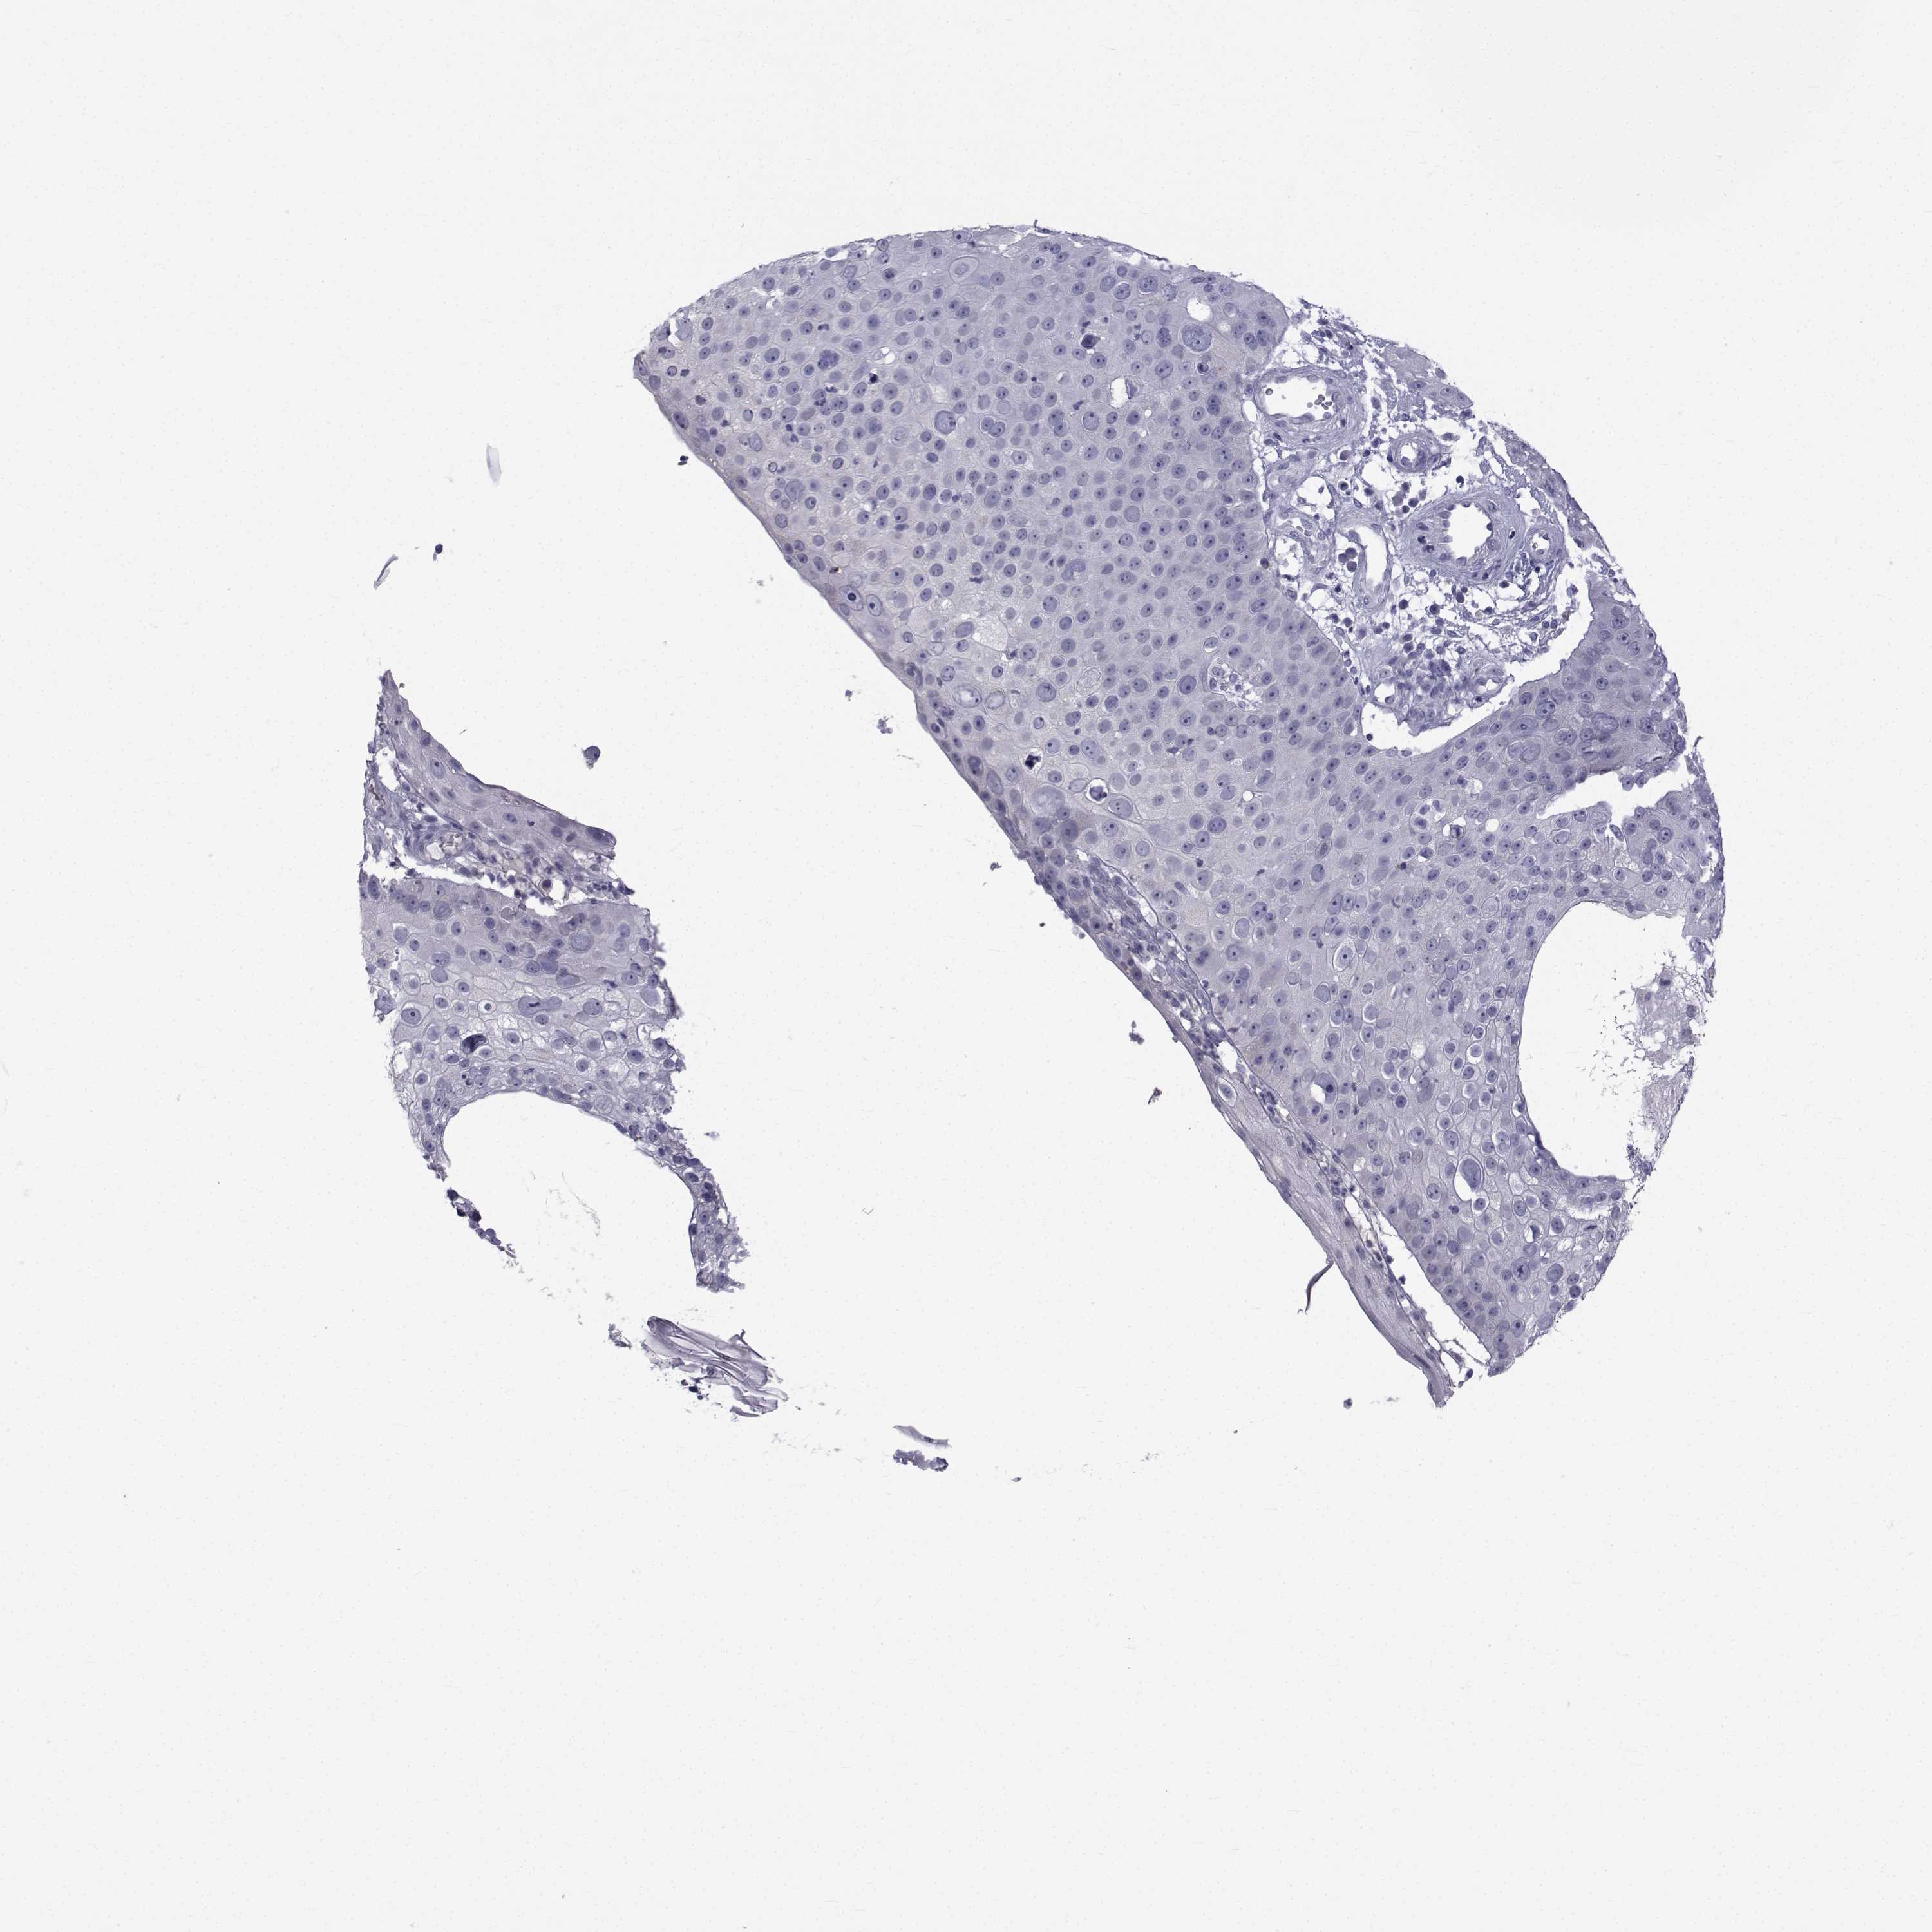

CANCER SKIN CANCER Show tissue menu

SKIN CANCER - Protein expressioni

A mouse-over function shows sample information and annotation data. Click on an image to view it in a full screen mode. Samples can be filtered based on level of antibody staining by selecting one or several of the following categories: high, medium, low and not detected. The assay and annotation is described here.

Each image is clickable and will lead to virtual microscopy that enables deeper exploration of all samples and also displays staining intensity scores, fraction scores and subcellular localization as well as patient and tissue information for each sample.

Antibody HPA044393

Squamous cell carcinoma, NOS

Basal cell carcinoma